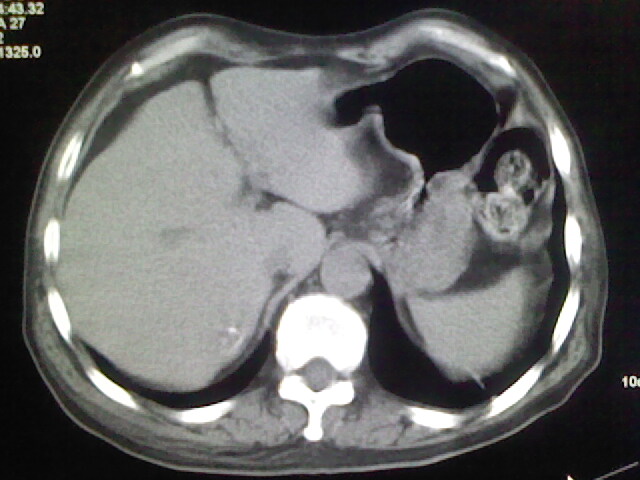

男,70岁,脑出血,长期卧床,左侧背部可触及肿块

背部没见到肿块呀,有感染灶。

肺部感染,背部筋膜增厚,考虑坠积性水肿或炎症

食道里是什么

你放上去的